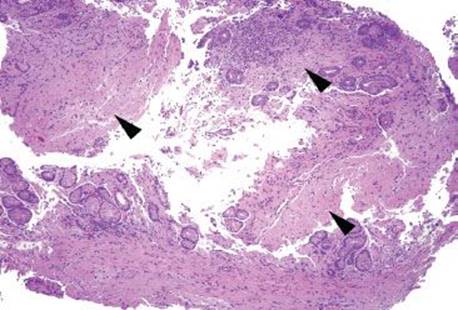

Figure 2.216 GAVE. In this remarkable case, a partial gastric resection was performed for GAVE refractory to endoscopic management. Numerous foci of hemorrhage and thrombi are seen at scanning magnification (brackets).